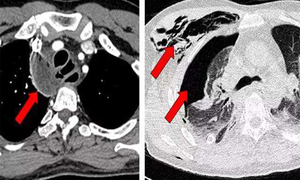

2、CT

X线检查有约10%的漏诊率,CT检查更能明确诊断,可以发现X线检查不能发现的纵隔气肿,不仅能直接观察到纵隔内气体密度影的存在,并能清晰分辨与周围结构关系,同时可显示胸壁及颈部有无皮下与深部组织间气肿存在,部分病例尚能发现诱发纵隔气肿的肺内基础病变。